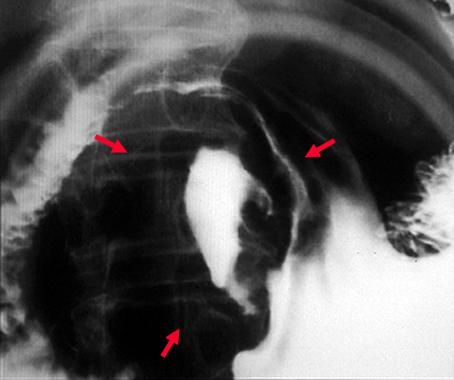

疾病(病理主体)的分类恶性上皮肿瘤/未分化癌

部位(按器官分)胃(部位)/前庭

检查方法X线

肿瘤的肉眼分类2型(溃疡局限型)/

肿瘤最大直径40以上

肿瘤的深度s(a)